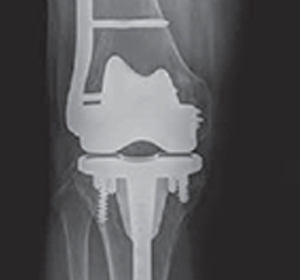

- Revision Prosthesis: When there is a loosening of the prosthesis, the whole implant will usually have to be surgically removed and replaced with a hinged knee prosthesis, which can be considered a salvage device that provides better stability to the knee.